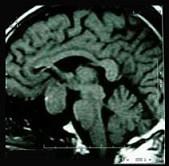

问题 垂体大腺瘤是指()

选项 A.直径>10cm的肿瘤 B.直径>10μm的肿瘤 C.直径>5cm的肿瘤 D.直径>10mm的肿瘤 E.直径>5mm的肿瘤

答案 D